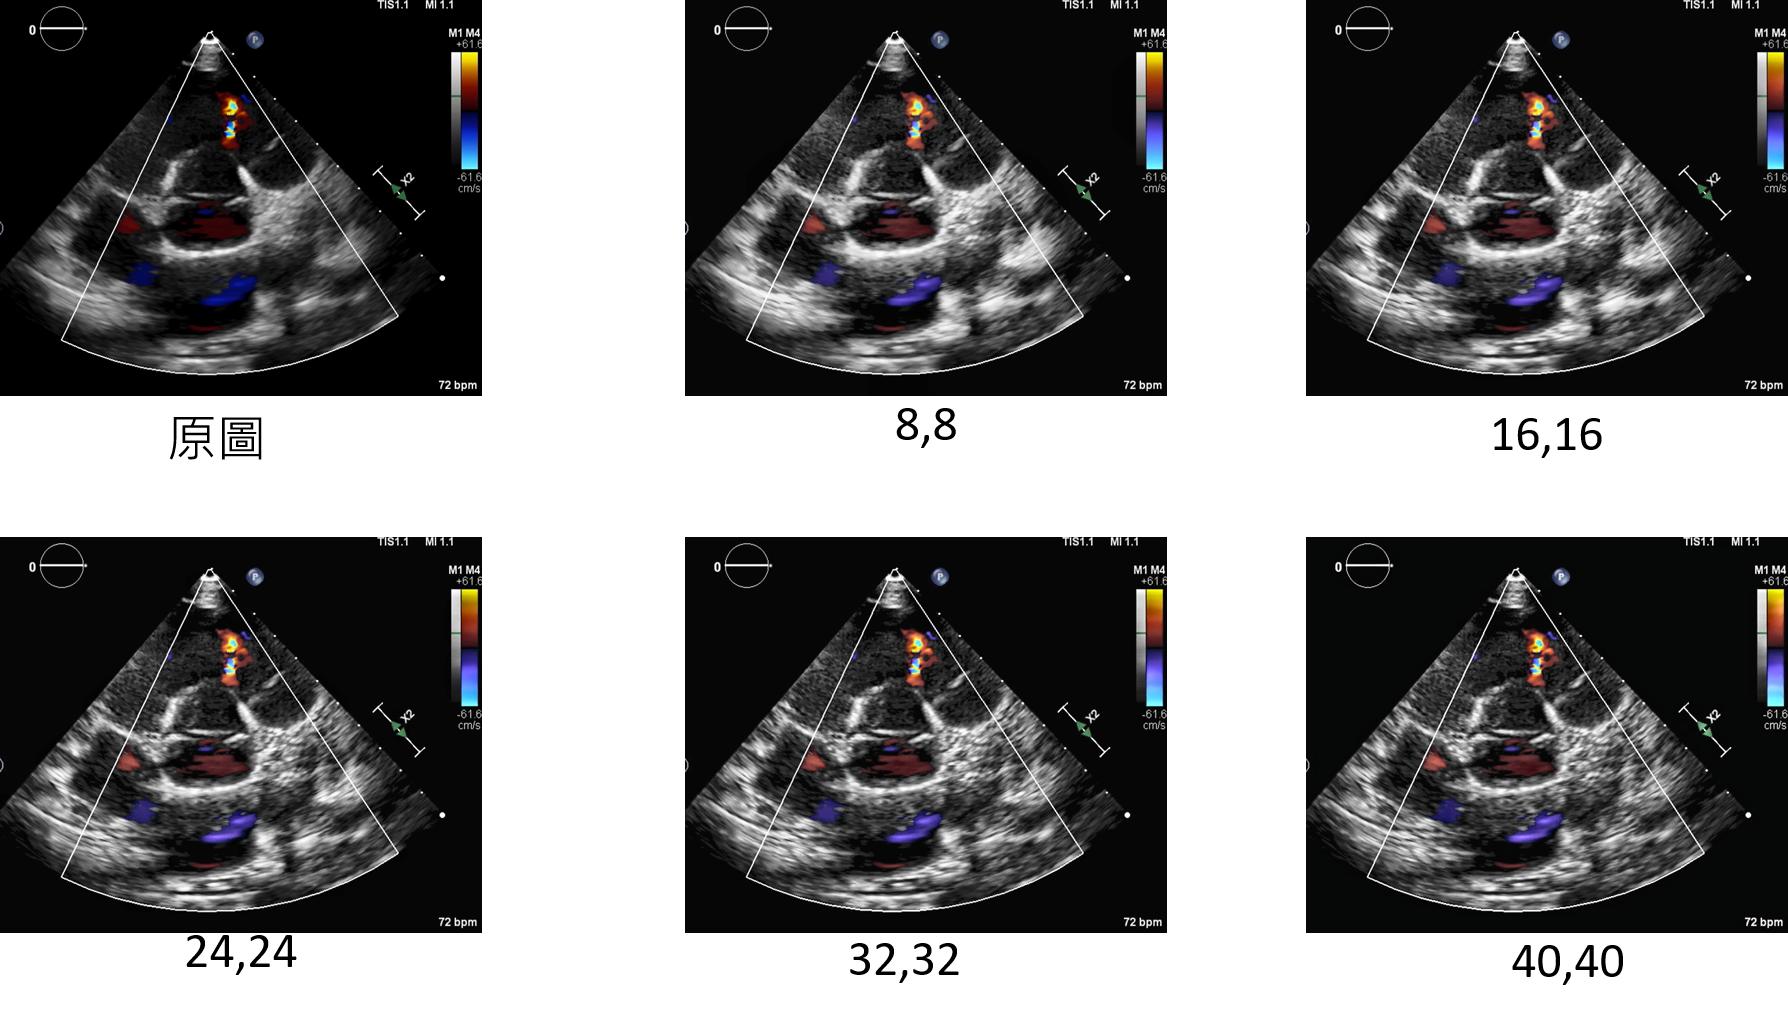

CLAHE_Color:增強方法

clahenum:設定每次處理的大小(值越大圖片顆粒感越重)

datagen=CustomDataGenerator(fun="CLAHE_Color",clahenum=40,dtype=int)

*下圖分別為clahenum所設定不同值的結果,由下圖所示clahenum設定為24輪廓較為明顯。